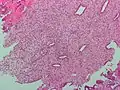

Low magnification micrograph of decidualized endometrium. H&E stain

The endometrium consists of a single layer of columnar epithelium plus the stroma on which it rests. The stroma is a layer of connective tissue that varies in thickness according to hormonal influences. In the uterus, simple tubular glands reach from the endometrial surface through to the base of the stroma, which also carries a rich blood supply provided by the spiral arteries. In women of reproductive age, two layers of endometrium can be distinguished. These two layers occur only in the endometrium lining the cavity of the uterus, and not in the lining of the fallopian tubes.[4][5]

If there is inadequate stimulation of the lining, due to lack of hormones, the endometrium remains thin and inactive. In humans, this will result in amenorrhea, or the absence of a menstrual period. After menopause, the lining is often described as being atrophic. In contrast, endometrium that is chronically exposed to estrogens, but not to progesterone, may become hyperplastic. Long-term use of oral contraceptives with highly potent progestins can also induce endometrial atrophy.[13][14]